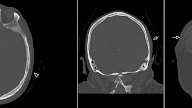

Deep Cerebral Venous Sinus Thrombosis with External Capsule Hemorrhage

Patient presented with acute hemorrhage in the right external capsule. Finding that was in the first place suspected for hypertension hemorrhage. However patient had no history of hypertension and just 5 days later developed another external capsule hemorrhage on the left side (second image). At this time there was also some diffuse low density noted in the basal ganglia suggesting extensive infarction. Following scan (third image) has shown advanced infarction extensively involving the basal ganglia. CT Cerebral Venous Angiography has revealed Deep Cerebral Venous Sinus Thrombosis. Note thrombus in sinus rectus (arrowheads). This is a case of Deep Cerebral Venous Sinus Thrombosis with External Capsule Hemorrhage. Teaching point here is that Cerebral Venous Thrombosis can manifest as hemorrhage. See my previous case of Sinus Thrombosis with SAB. Another important teaching point is that large infarctions in the basal ganglia can be associated with Deep Cerebral Sinus Thrombosis.